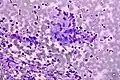

Micrograph of a Field stain showing malignant melanoma.

Field stain is a histological method for staining of blood smears. It is used for staining thick blood films in order to discover malarial parasites. Field's stain is a version of a Romanowsky stain, used for rapid processing of the specimens.[1]

Field's stain consists of two parts - Field's stain A is methylene blue and Azure 1 dissolved in phosphate buffer solution; Field's stain B is Eosin Y in buffer solution. Field stain is named after physician John William Field, who developed it in 1941.[2]